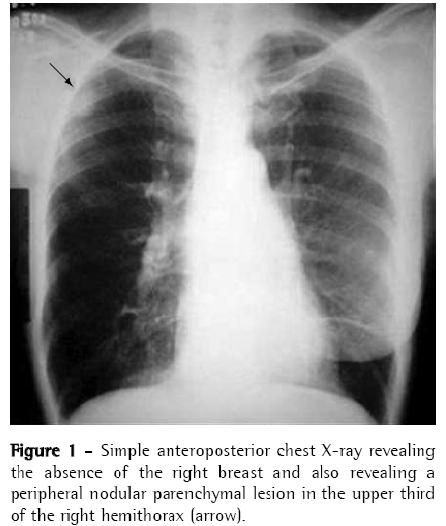

The patient then underwent computed tomography of the chest, which revealed a pleural, parenchymal pulmonary nodule measuring approximately 30 × 25 mm (Figure 2) in the right lung. Therefore, a hypothetical diagnosis of pulmonary metastasis of the breast carcinoma previously removed was made, and biopsy was indicated for diagnostic confirmation.

The anatomopathological examination revealed that it was a non-capsulated, regular lesion measuring 30 × 25 mm and presenting a firm and fibroelastic consistency. Microscopy (Figure 3) revealed vessels, adipose tissue, cartilage, well-differentiated (but disorganized) bronchial structures, and highly vascularized fibrovascular stroma with interposed embryonic bronchi, compatible with pulmonary hamartoma.